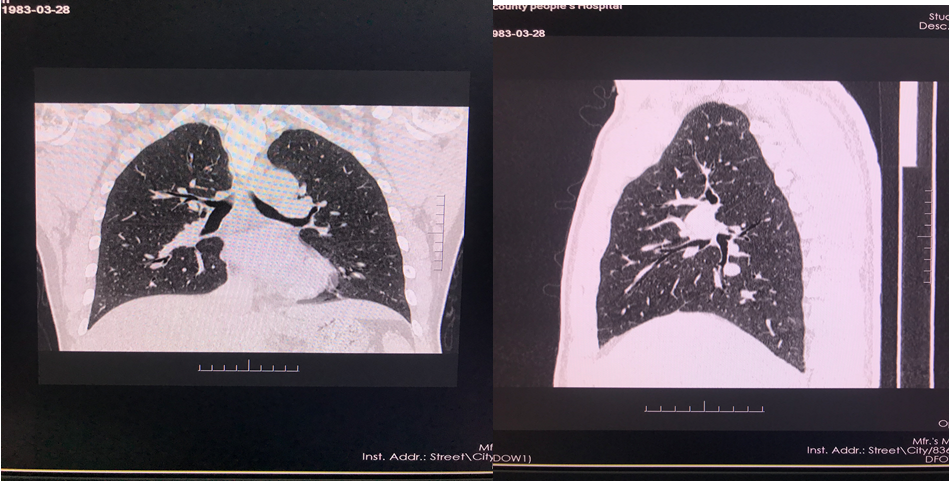

四、开展项目:科室现常规开展全身各部位CT平扫及增强检查、CT三维重建、CT血管造影(CTA、CTV)、(包括冠状动脉CTA)、CT尿路造影(CTU)、全身各部位DR摄片检查、床边摄片、同时开展胆系T管造影、CT定位下穿刺活检。